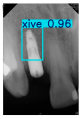

However, since the implant launched onto the market, dental treatment related to implant issues has become the everyday practice of dentists’ lives in clinics [10]. The design of the implants, from shape to surface coating, is different from brand to brand [11]. But it is inevitable to come into implant complications [12,13], such as screw fracture, healing abutment loss, etc., whether the clinician itself treats the implant or implant prosthesis. Different surface coatings [14,15] and threads of the implant design [16,17] may be easily identified in vitro. Moreover, once the implants are in vivo, the clinicians can only identify implant brands through radiography or the clinicians’ familiarity with the implant. If the clinicians are not familiar with the brands, then it is hard to tell which brand the implant is from in vivo. As the number of implant brands on the global market grows, it has become increasingly complex for clinicians to identify and familiarize themselves with all available implant systems accurately. 3i and Xive are two of the most widely used and clinically validated implant brands worldwide, with excellent long-term success rates [18] and reliable implant-abutment connection designs [19]. Therefore, we strategically focused on 3i and Xive implants in this study to ensure clinical relevance and practical significance. Concentrating on these two brands allows our model to address many real-world clinical cases and enhances its applicability in everyday dental practice. Clinicians will likely encounter both implant brands due to their widespread use in global dental clinics [20]. Moreover, as the implant’s screwdrivers differ from brand to brand, the identification of implant brands is very important to clinicians and patients. The marginal accuracy of the implant-abutment connection may vary due to misidentification and lead to unknown clinical problems [21,22]. The PA imaging results of two implant brands of different types at different resolutions (R) are shown in Figure 1. These two commonly used implant brands exhibit highly similar characteristics, with the most apparent difference being the variation in implant threading patterns. However, this distinction is not easily discernible for PA datasets.

Figure 1.

Imaging of two implant brands at different resolutions.